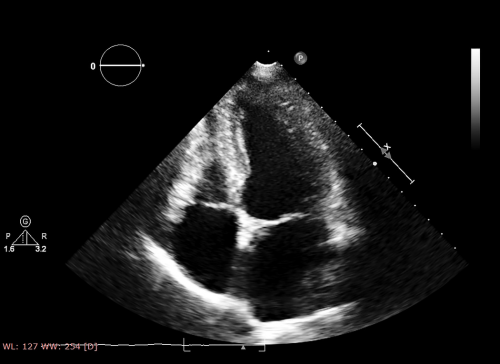

1.基本断面の描出法と注意点

1.心機能計測のポイントと注意点